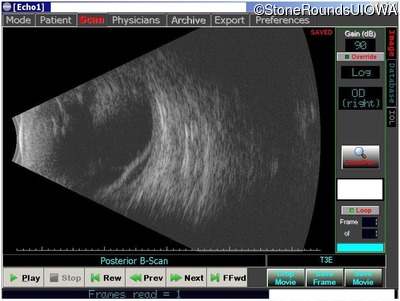

Visit at age: 46 years (Visit 2)

B-Scan Ultrasonography - Left - unknown

Exemplar